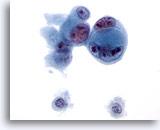

画像 3

肝FNA – 良性肝細胞

核はわずかに大小不同であり、反応性変化を来した肝細胞に典型的な低N/C比を示します。微小な細胞質空胞および細胞質内色素がみられます。

60倍

画像 3

肝FNA – 良性肝細胞

核はわずかに大小不同であり、反応性変化を来した肝細胞に典型的な低N/C比を示します。微小な細胞質空胞および細胞質内色素がみられます。

60倍